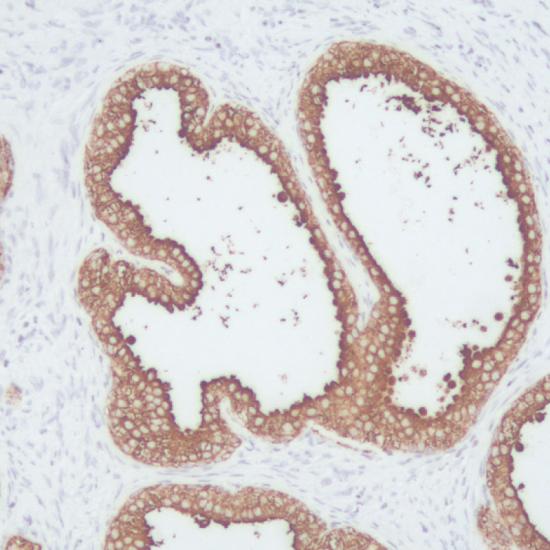

PSA抗體試劑(免疫組織化學(xué)) 閩廈械備20180110號

• 陽性部位:

細(xì)胞漿

• 陽性對照:

前列腺癌

前列腺特異抗原(PSA)是一種分子量為32kD的單鏈糖蛋白,由前列腺上皮細(xì)胞分泌產(chǎn)生,它是一種酷似糜蛋白酶的絲氨酸蛋白酶。PSA具有組織特異性,只存在于人前列腺腺泡及導(dǎo)管上皮細(xì)胞胞漿中,不表達(dá)于其它細(xì)胞。但它并無腫瘤特異性,前列腺炎、良性前列腺增生和前列腺癌均有表達(dá)。